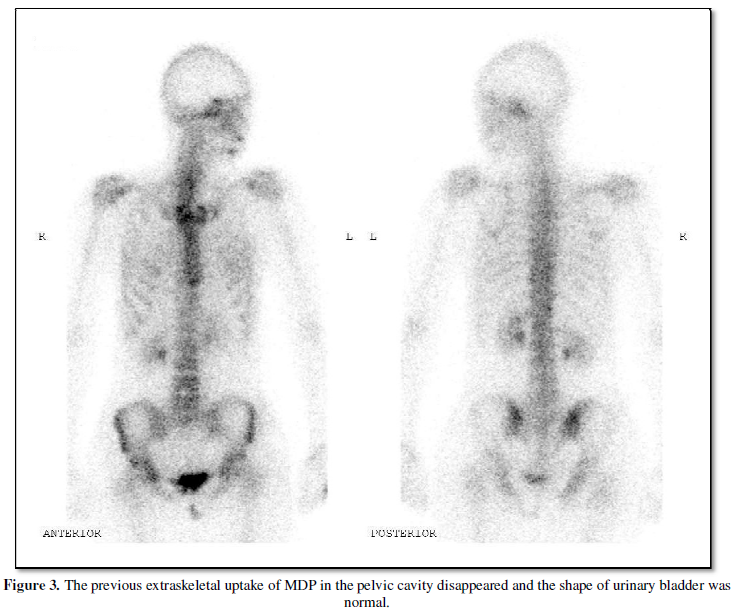

largest measured up to 7 cm in diameter. The bone scan was repeated after the

hysterectomy. The previous extraskeletal uptake of MDP in the pelvic cavity

disappeared and the shape of the urinary bladder was normal (Figure 3).